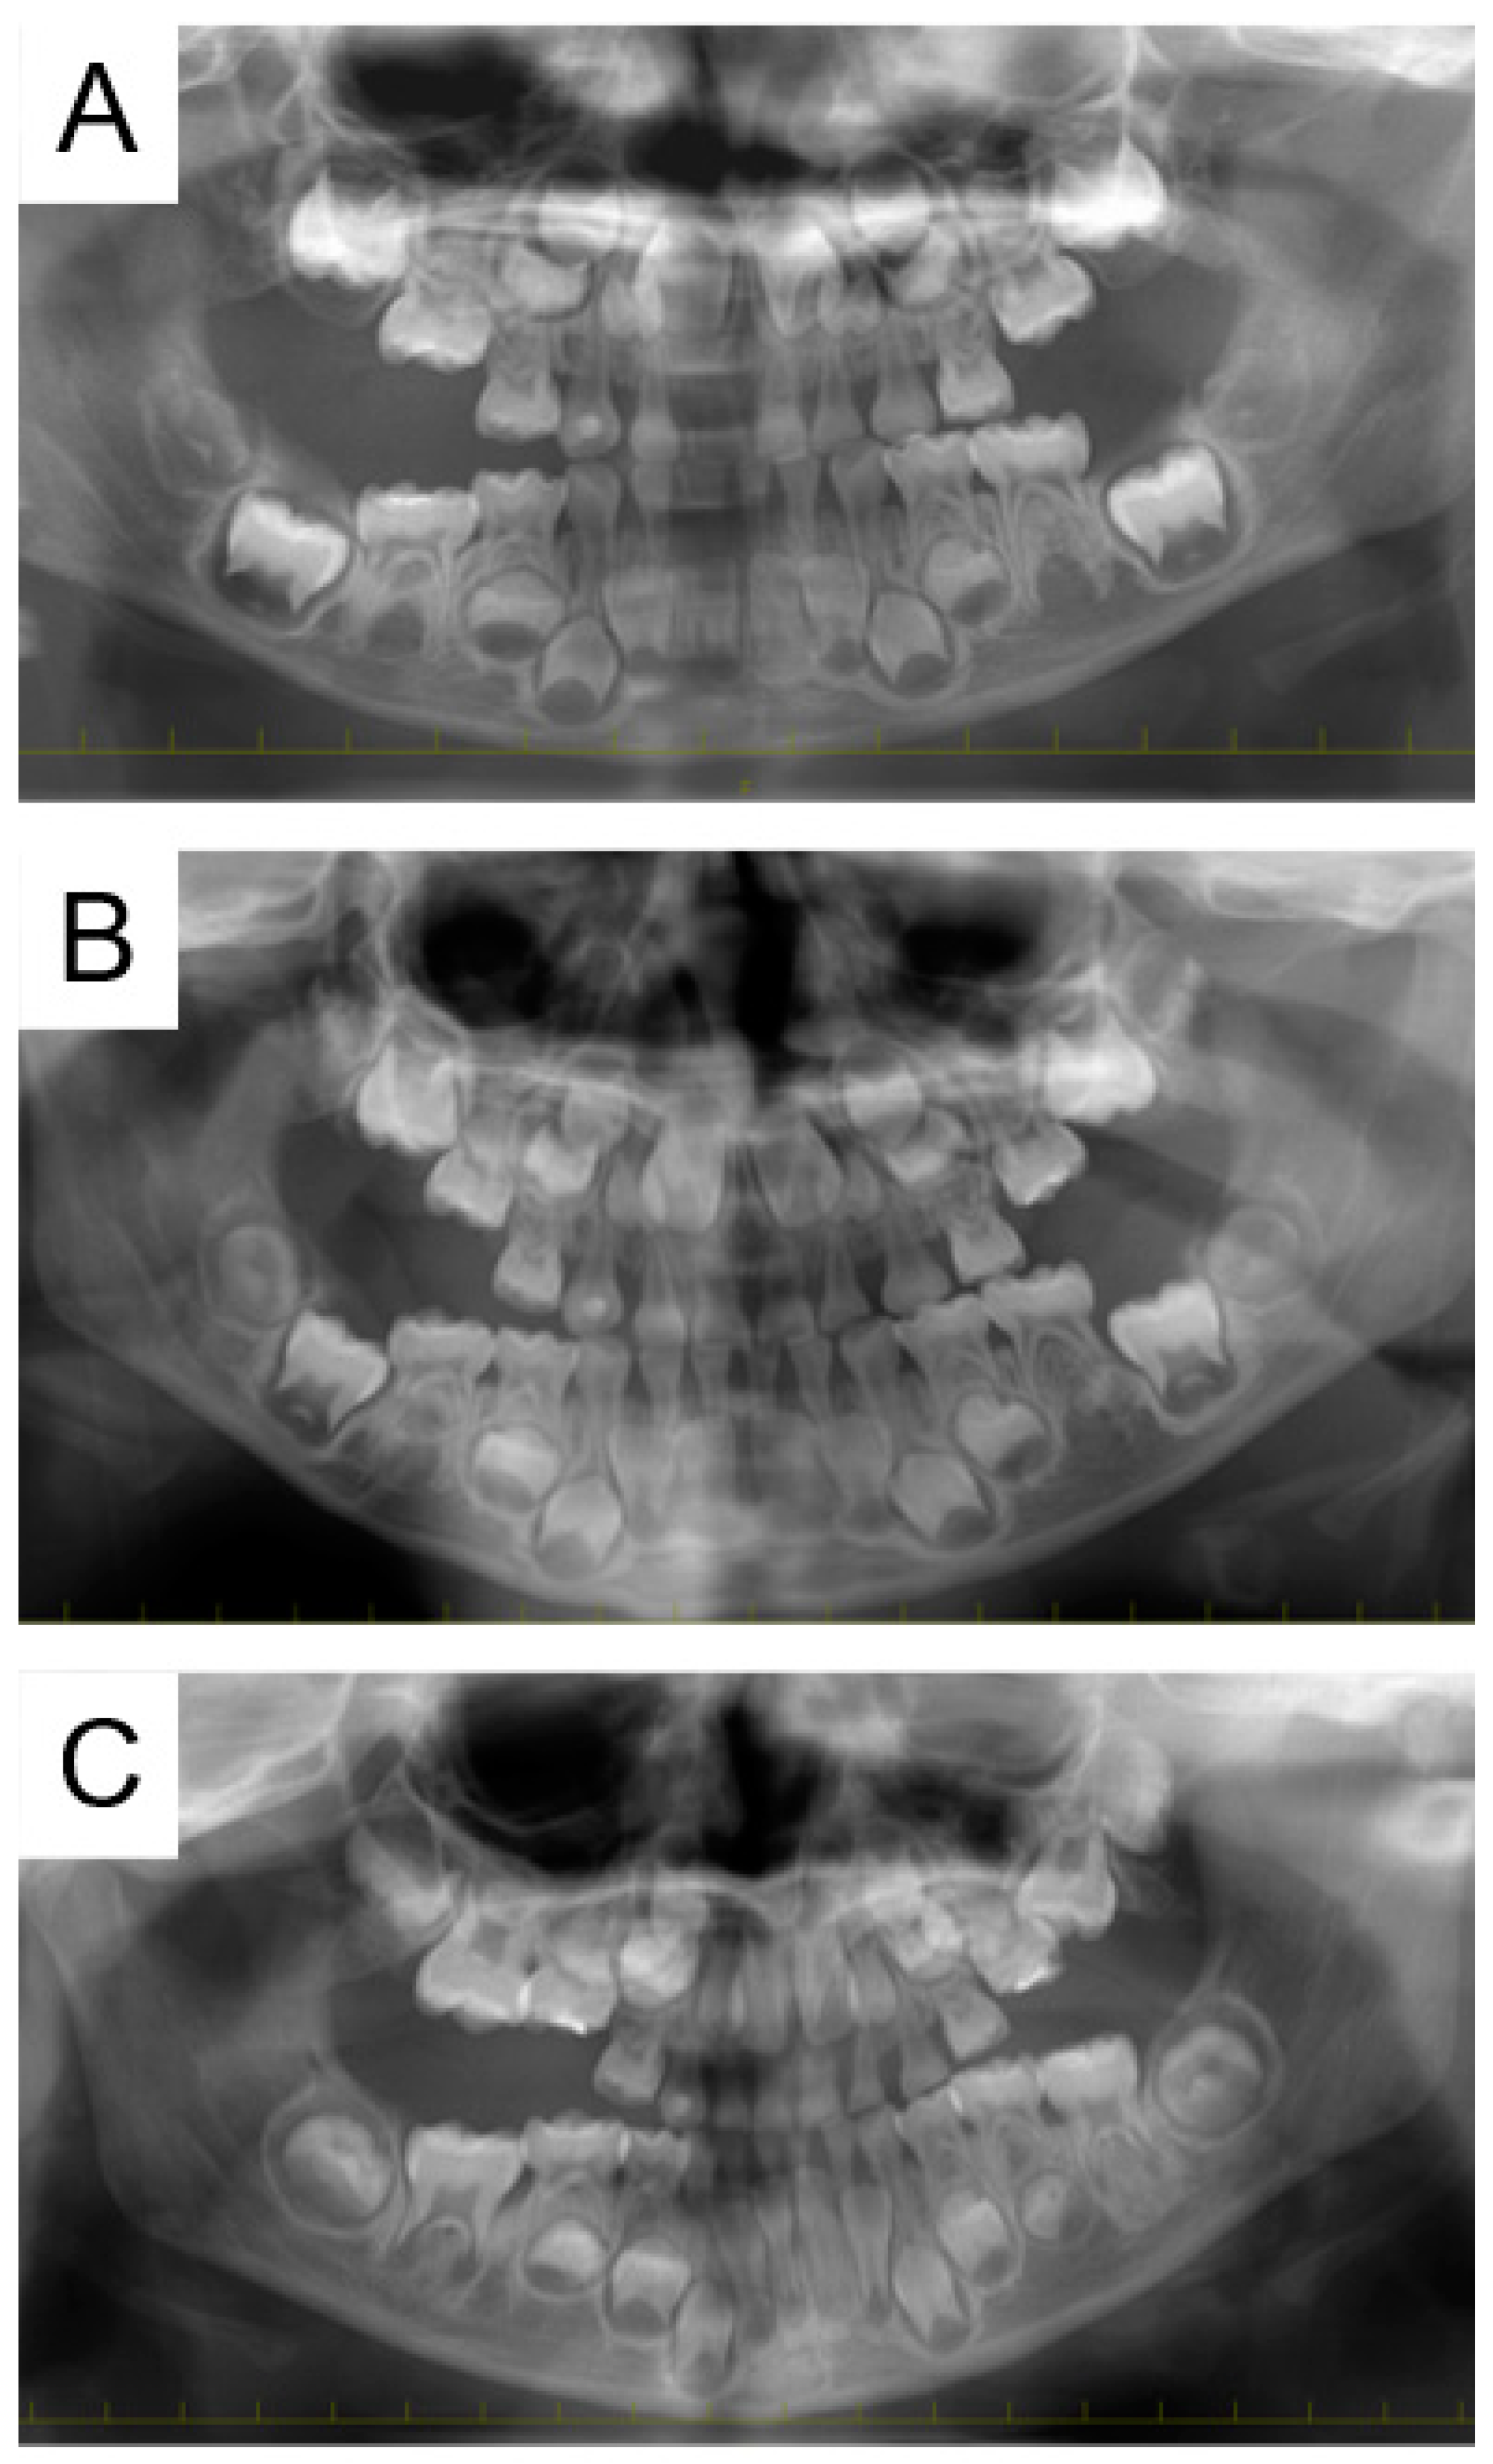

2.1. Case 1

2.2. Case 2